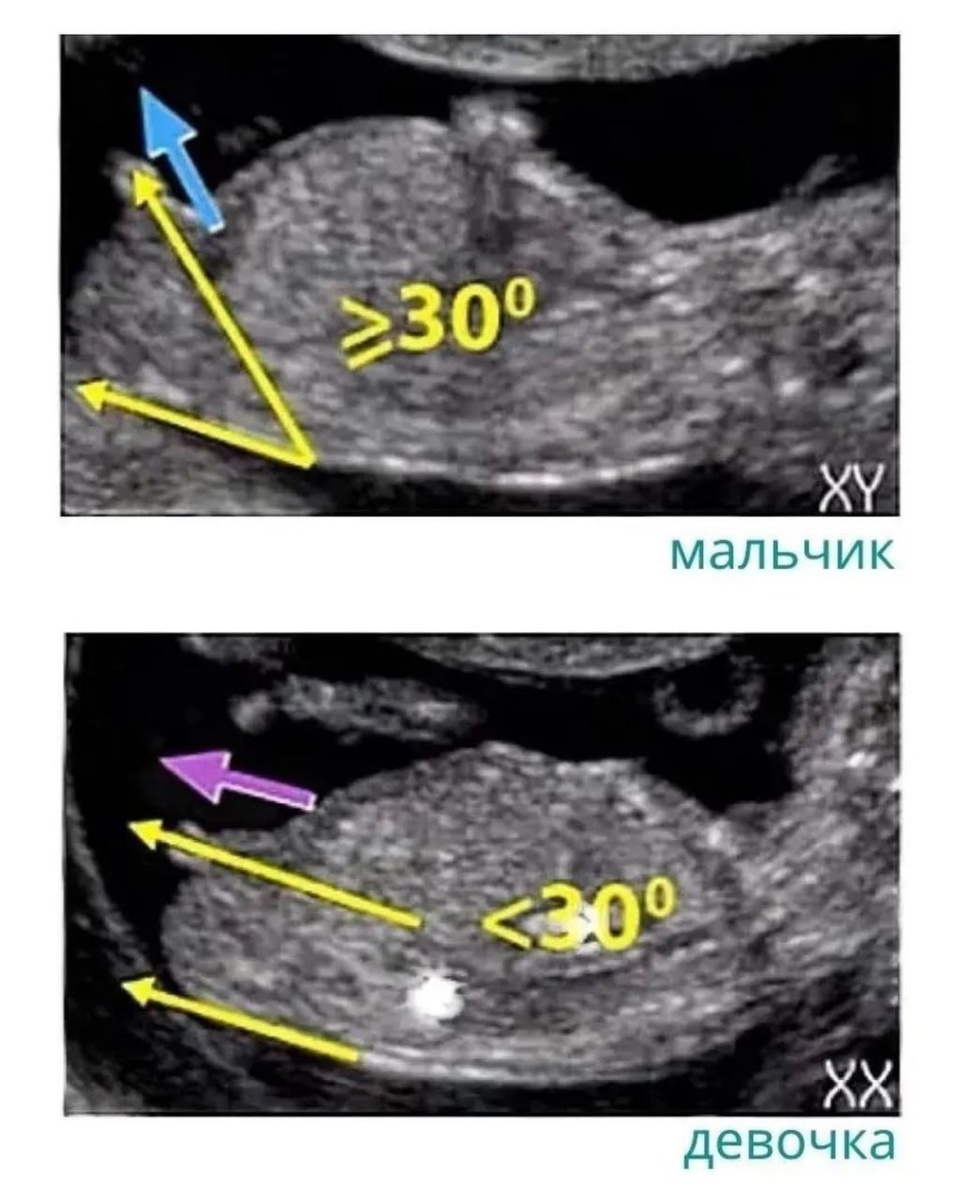

🔆 Угол, образованный спинкой ребенка и его половым бугорком.

На девочку указывает угол менее 30°. А если угол больше – мальчик.